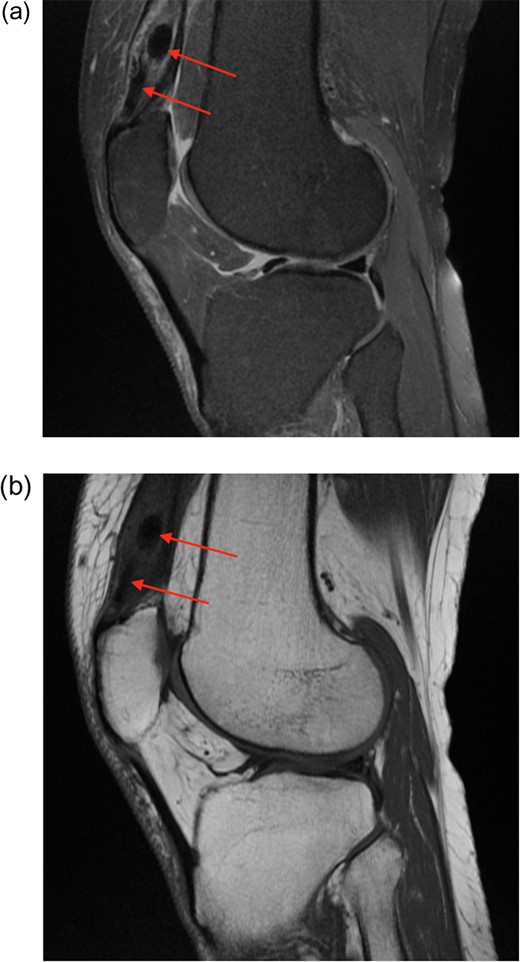

(a) Proton density fat saturated (PDfs) sagittal MRI. There is enlargement of the distal quadriceps tendon, with splayed fibres separated by solid low signal foci. (b) T1 sequence MRI also showing low signal lesions.